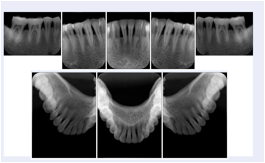

3. A patient in rural Minnesota experiences sudden vision loss and goes to a general ophthalmologist, who acquires OCT images and forwards them electronically along with a Structured Display to a retina specialist six travel hours away. The retina specialist is able to view the images in the standard layout that he is comfortable with, and to confirm that the patient has a choroidal neovascular membrane. He determines that is would be worthwhile for the patient to travel for treatment.

OCT Retinal Study with Cross Section and Navigation Structured Display

Figure OO-4. OCT Retinal Study with Cross Section and Navigation Structured Display